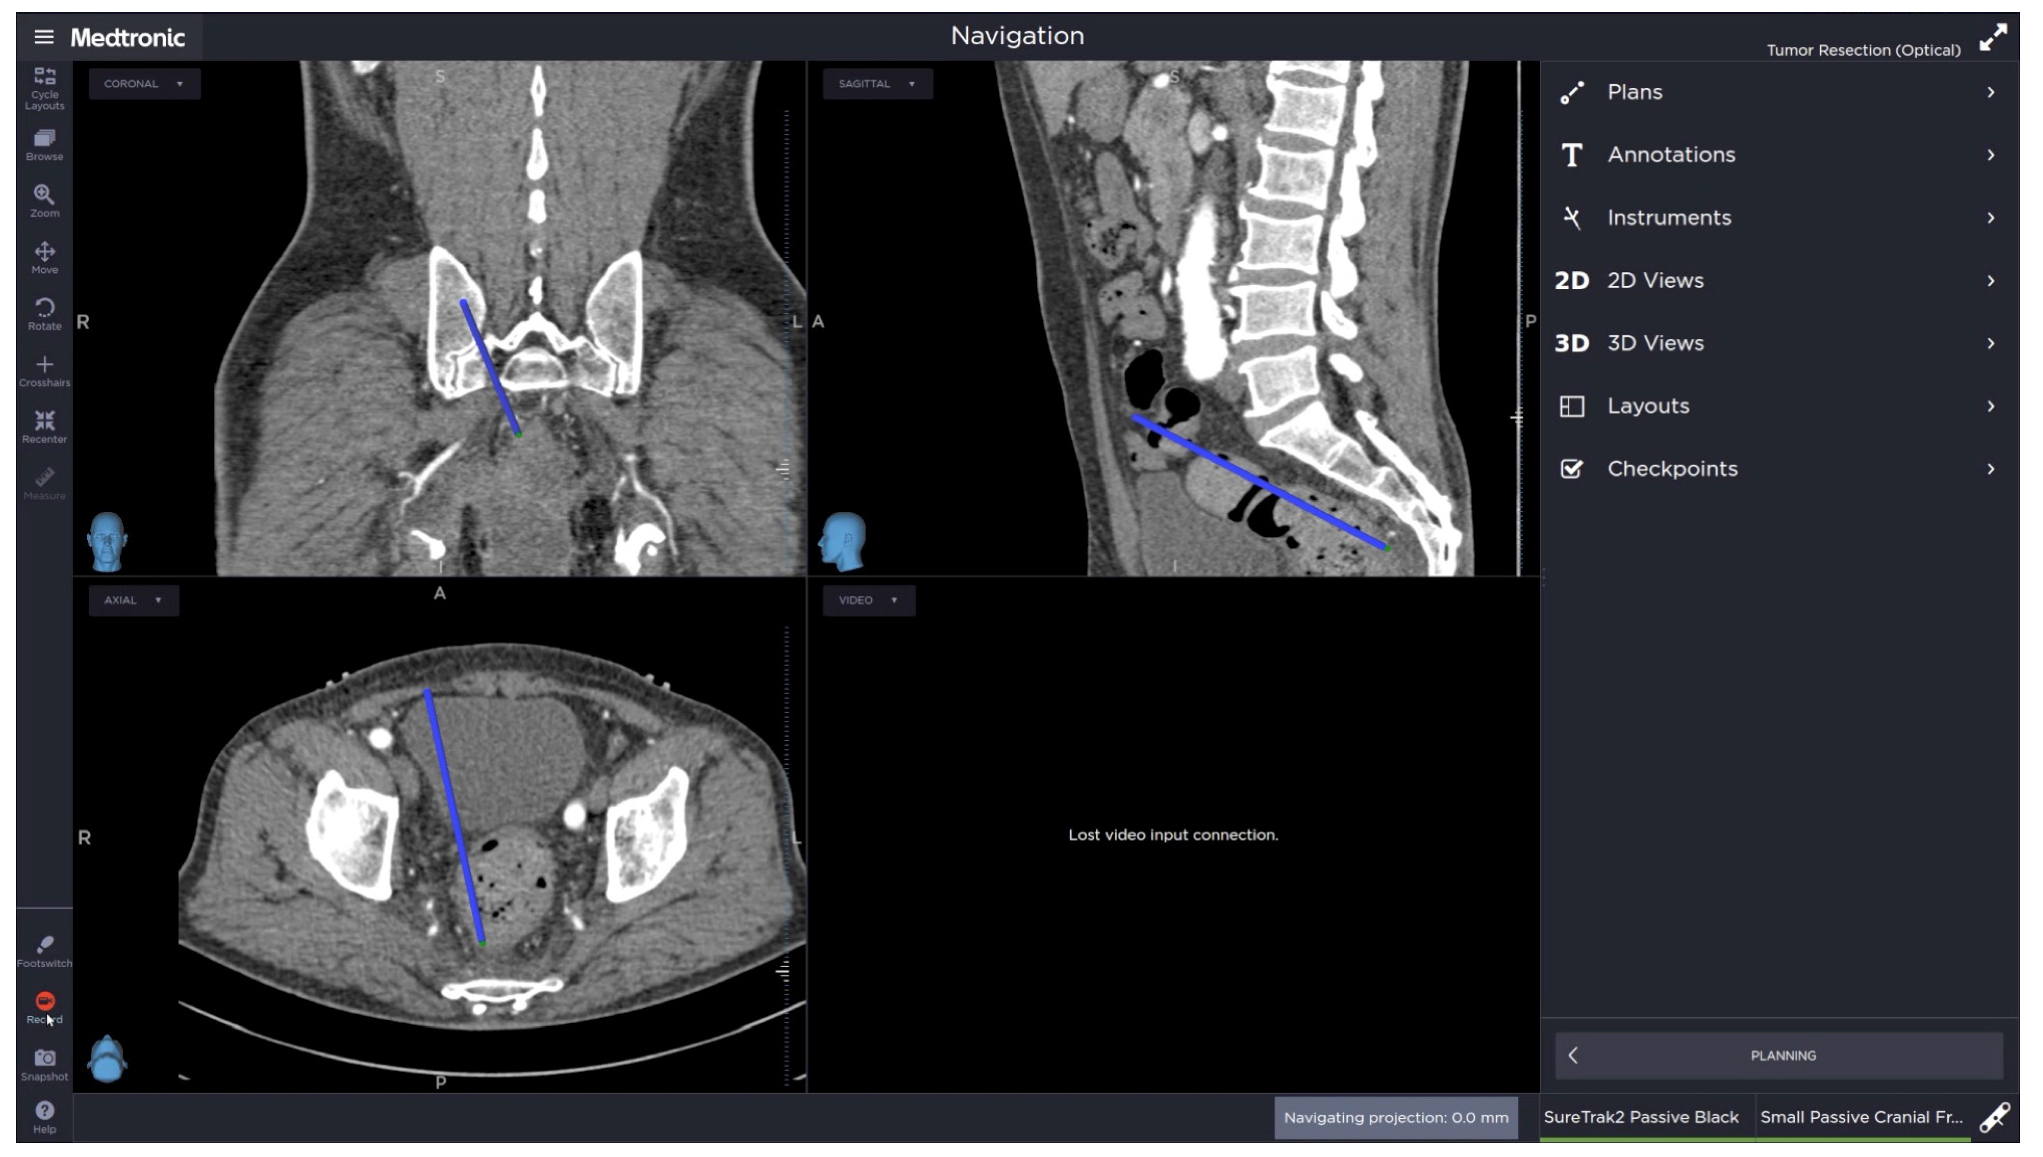

3. Results